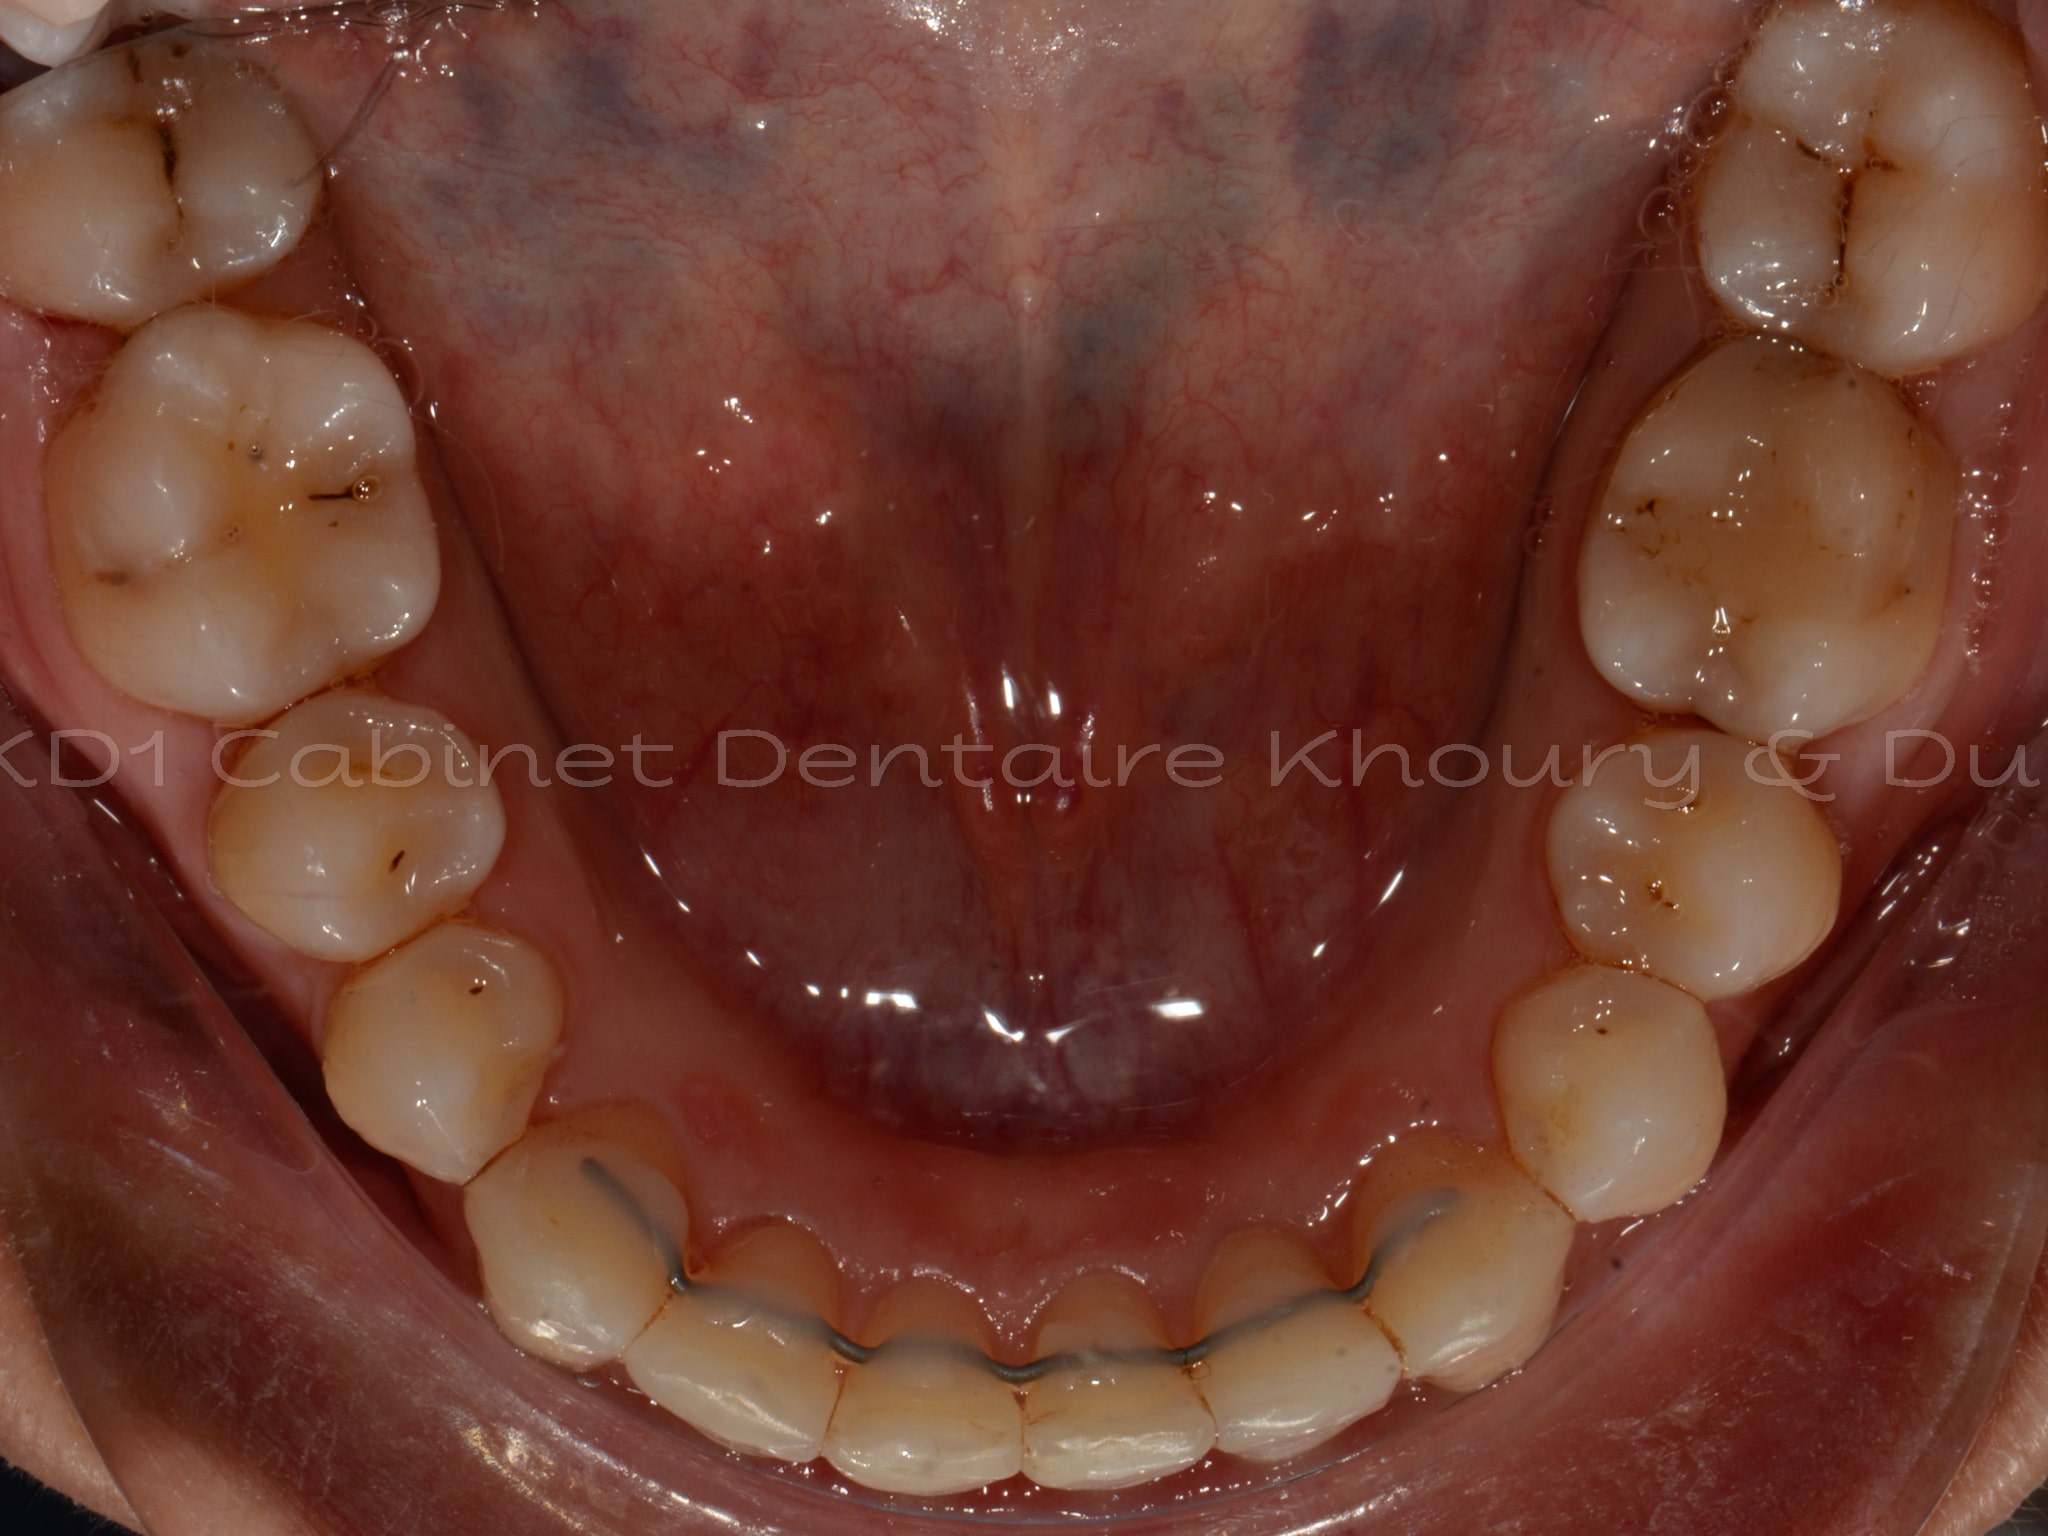

Cas #1 – Traitement avec des bagues, deuxièmes prémolaires et dent de sagesse supérieures ectopiques.